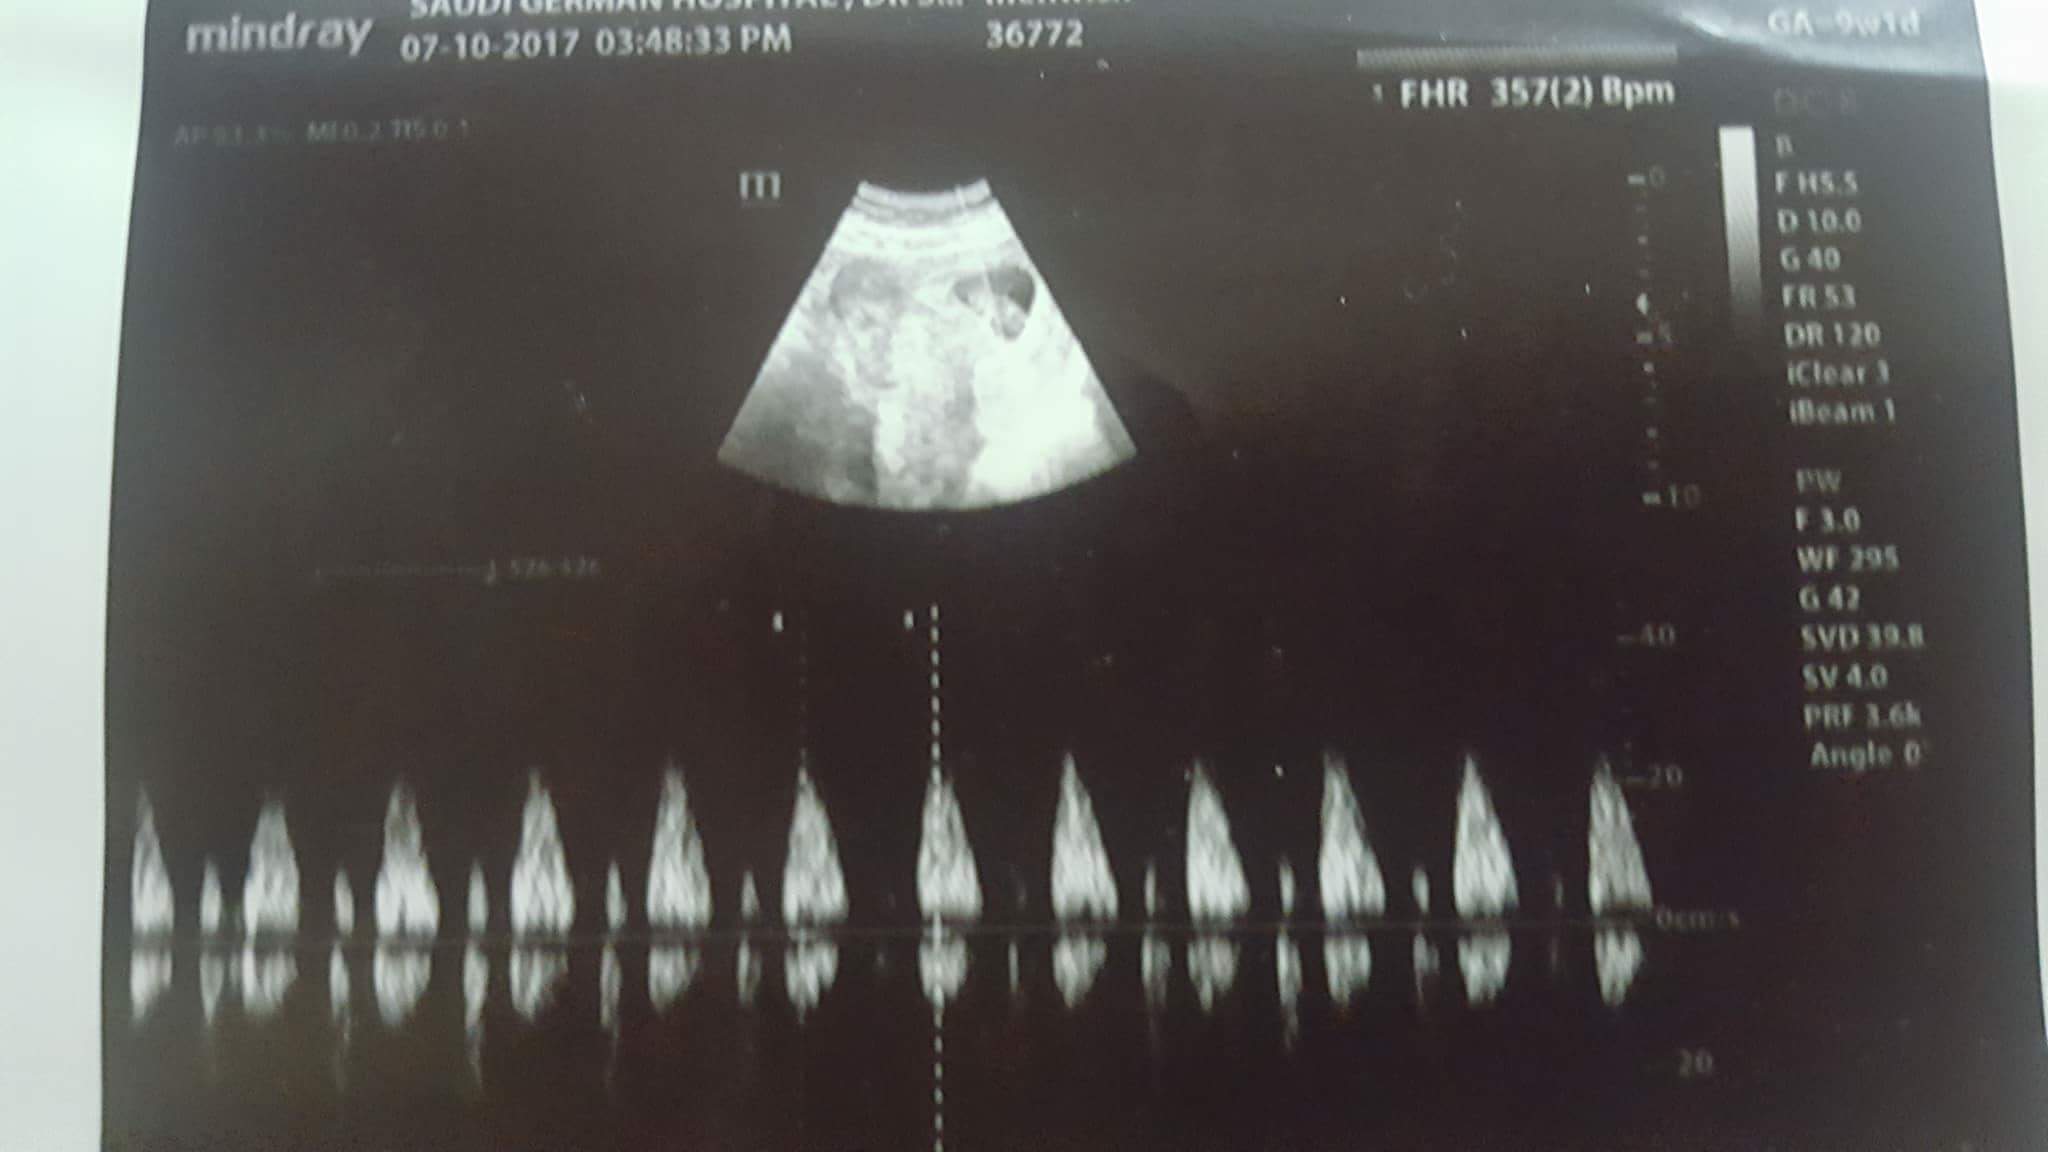

I am 9 weeks, had an ultrasound due to extreme dizziness and headache. Everything was fine.. baby was already moving, there was good heartbeat.

When I came home and showed ultrasound to my husband he pointed at second sac and asked me about it.. I don't know how I didn't notice it. My obgyn never said anything about twins. She did said there is no bleeding now! So it means second sac looking thing is not a blood. Wat is it? A hidden twin?

Attachment 37892